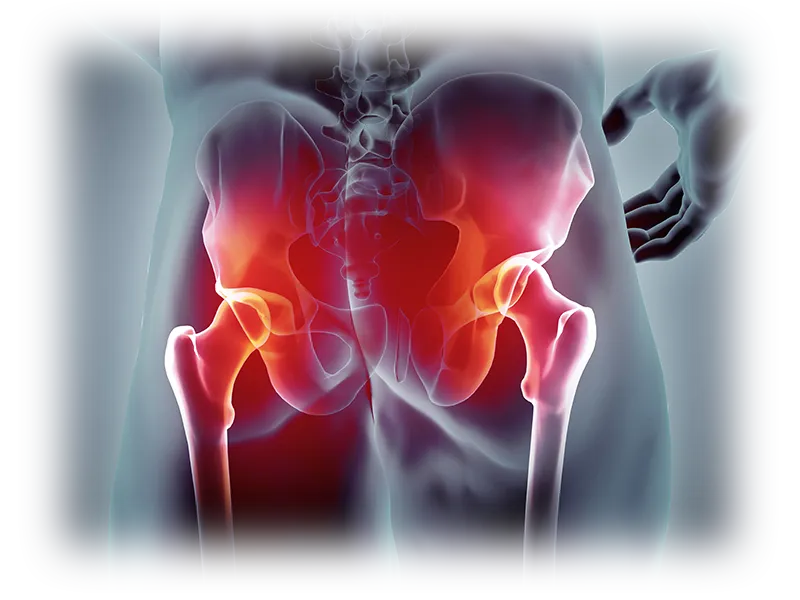

고관절은 엉덩이 관으로도 알려져 있으며, 인체에서 가장 큰 관절입니다. 그러므로 고관절에 문제가 생기면 종종 무릎 관절 문제보다 더 심각한 결과와 증상을 초래하는 경우가 많습니다. 무릎에 통증이 있는 경우 목발이나 다른 보조 기구를 통해 이동이 가능하지만, 고관절 장애는 종종 사람을 완전히 움직이지 못하게 할 수 있습니다.

고관절은 골반과 대퇴골을 연결하여 척추와 체중을 지탱하고 하체를 지지하는 역할을 수행하며, 지속적인 압력을 받는 취약한 부위입니다. 걸을 때는 체중의 약 4배, 달리기를 할 때는 약 5배, 계단을 오를 때는 최대 8배의 하중이 고관절에 가해져 통증이나 질환이 발생하기 쉬운 부위입니다.